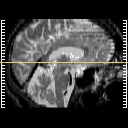

Click on sagittal image to select slice. Click on thin tickmark to change timepoint, or thick tickmark for overlay.